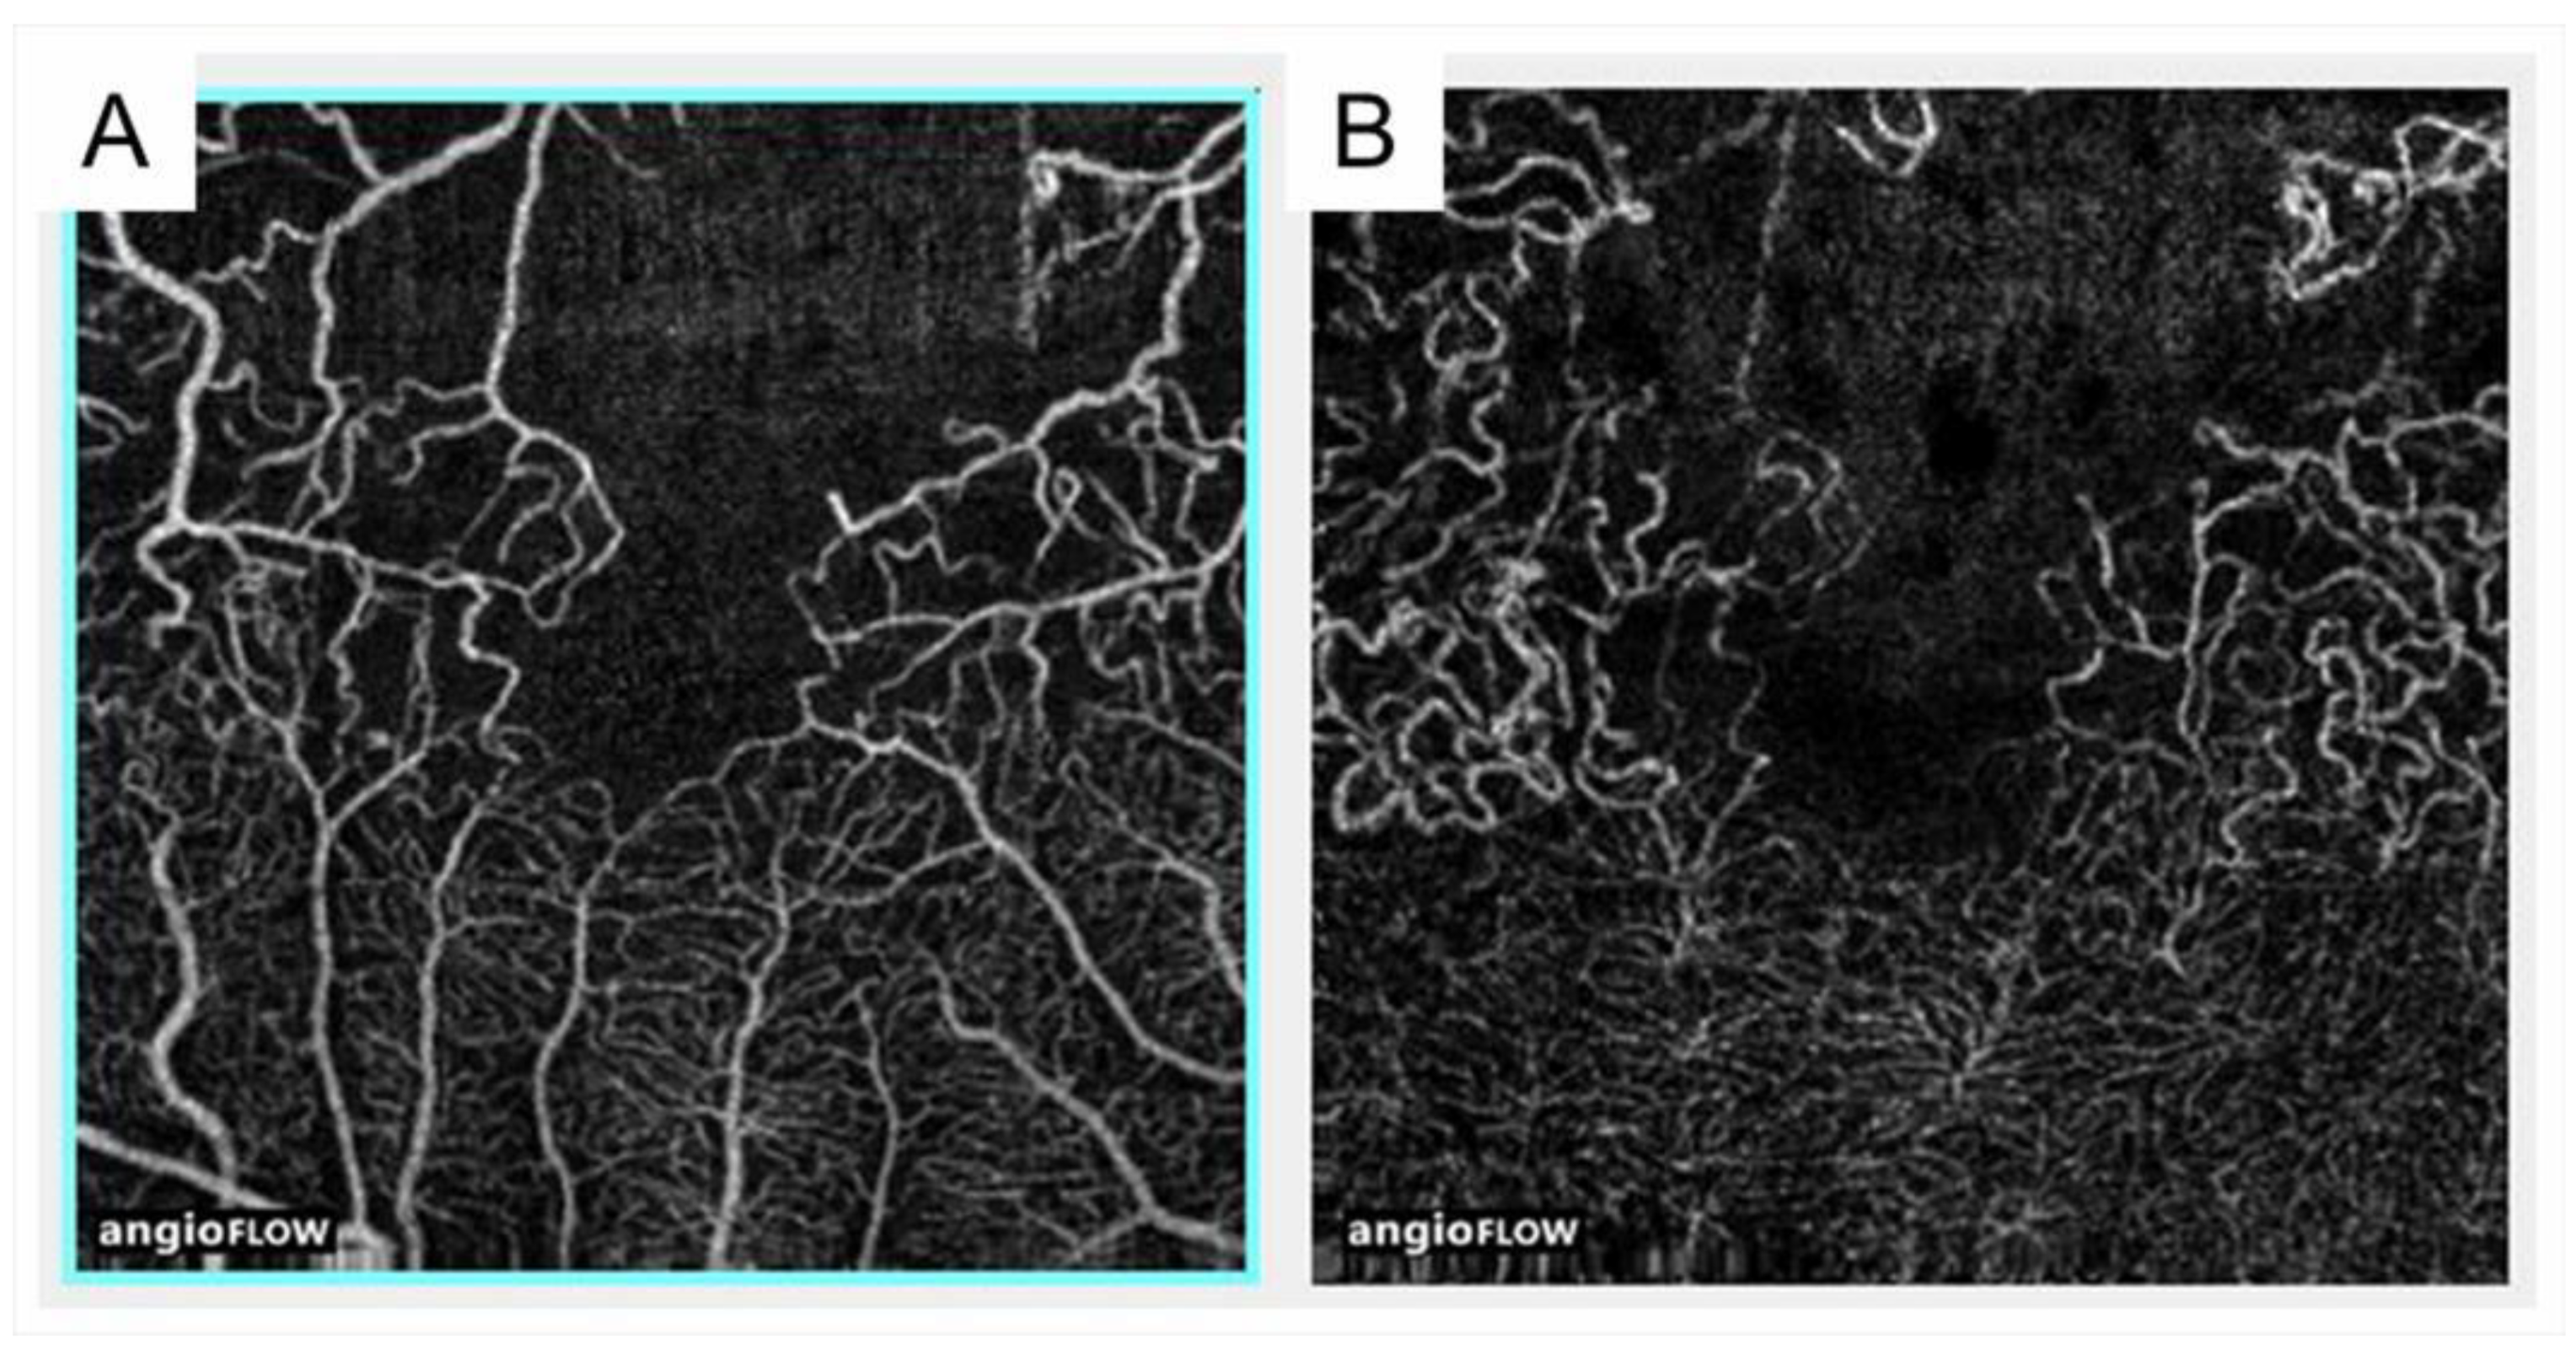

3.5. Foveal Avascular Zone: The Enlargement and the Circularity

- Samara, W.A.; Shahlaee, A.; Sridhar, J.; Khan, M.A.; Ho, A.C.; Hsu, J. Quantitative optical coherence tomography angiography features and visual function in eyes with branch retinal vein occlusion. Am. J. Ophthalmol. 2016, 166, 76–83. [Google Scholar] [CrossRef]

- Balaratnasingam, C.; Inoue, M.; Ahn, S.; McCann, J.; Dhrami-Gavazi, E.; Yannuzzi, L.A.; Freund, K.B. Visual acuity is correlated with the area of the foveal avascular zone in diabetic retinopathy and retinal vein occlusion. Ophthalmology 2016, 123, 2352–2367. [Google Scholar] [CrossRef]

- Wakabayashi, T.; Sato, T.; Hara-Ueno, C.; Fukushima, Y.; Sayanagi, K.; Shiraki, N.; Sawa, M.; Ikuno, Y.; Sakaguchi, H.; Nishida, K. Retinal Microvasculature and Visual Acuity in Eyes With Branch Retinal Vein Occlusion: Imaging Analysis by Optical Coherence Tomography Angiography. Investig. Ophthalmol. Vis. Sci. 2017, 58, 2087–2094. [Google Scholar] [CrossRef] [PubMed]

- Seknazi, D.; Coscas, F.; Sellam, A.; Rouimi, F.; Coscas, G.; Souied, E.H.; Glacet-Bemard, A. Optical coherence tomography angiography in retinal vein occlusion: Correlations between macular vascular density, visual acuity, and peripheral nonperfusion area on fluorescein angiography. Retina 2018, 38, 1562–1570. [Google Scholar] [CrossRef] [PubMed]

- Coscas, F.; Glacet-Bernard, A.; Miere, A.; Caillaux, V.; Uzzan, J.; Lupidi, M.; Coscas, G.; Souied, E.H. Optical Coherence Tomography Angiography in Retinal Vein Occlusion: Evaluation of Superficial and Deep Capillary Plexa. Am. J. Ophthalmol. 2016, 161, 160–171.e2. [Google Scholar] [CrossRef] [PubMed]